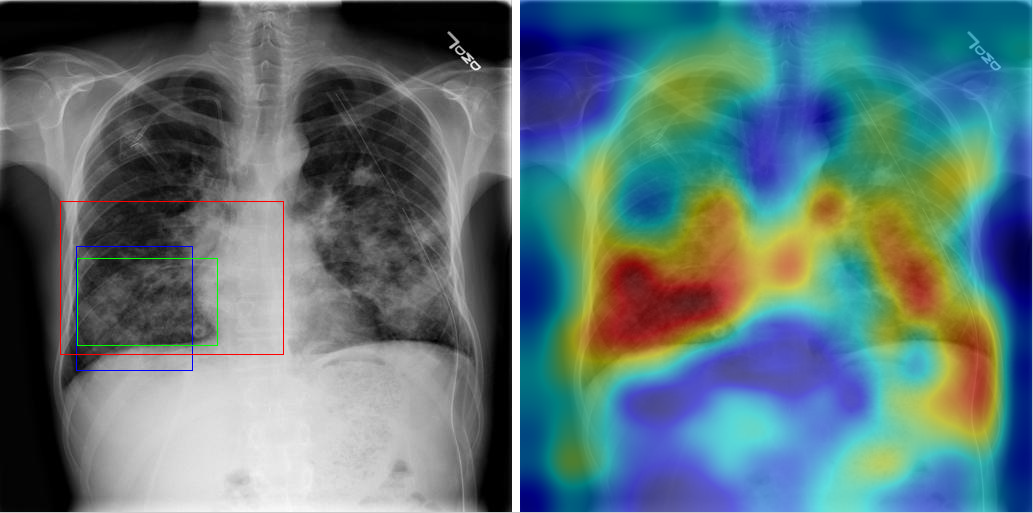

Table 8 to Table 15 illustrate localization results from each of 8 disease classes together with associated report and mined disease keywords. The heatmaps overlay on the original images are shown on the right. Correct bounding boxes (in green), false positives (in red) and the groundtruth (in blue) are plotted over the original image on the left.

In order to quantitatively demonstrate how informative those heatmaps are, a simple two-level thresholding based bounding box generator is adopted here to catch the peaks in the heatmap and later generated bounding boxes can be evaluated against the ground truth. Each heatmap will approximately results in 1-3 bounding boxes. We believe the localization accuracy and AFP (shown in Table 7) could be further optimized by adopting a more sophisticated bounding box generation method, e.g. selective search [47] or Edgebox [18]. Nevertheless, we reserve the effort to do so, since our main goal is not to compute the exact spatial location of disease patterns but just to obtain some instructive location information for future applications, e.g. automated radiological report generation. Take the case shown in Table 8 for an example. The peak at the lower part of the left lung region indicates the presence of “atelectasis”, which confer the statement of “…stable abnormal study including left basilar infilrate/atelectasis, …” presented in the impression section of the associated radiological report. By combining with other information, e.g. a lung region mask, the heatmap itself is already more informative than just the presence indication of certain disease in an image as introduced in the previous works, e.g. [42].

Radiology report Keyword Localization Result

findings: no appreciable change since XX/XX/XX. small right pleural effusion. elevation right hemidiaphragm. diffuse small nodules throughout the lungs, most numerous in the left mid and lower lung. impression: no change with bilateral small lung metastases. Effusion; Nodule [Uncaptioned image]

Table 10: A sample of chest x-ray radiology report, mined disease keywords and localization result from the “Effusion” Class. Correct bounding box (in green), false positives (in red) and the ground truth (in blue) are plotted over the original image.